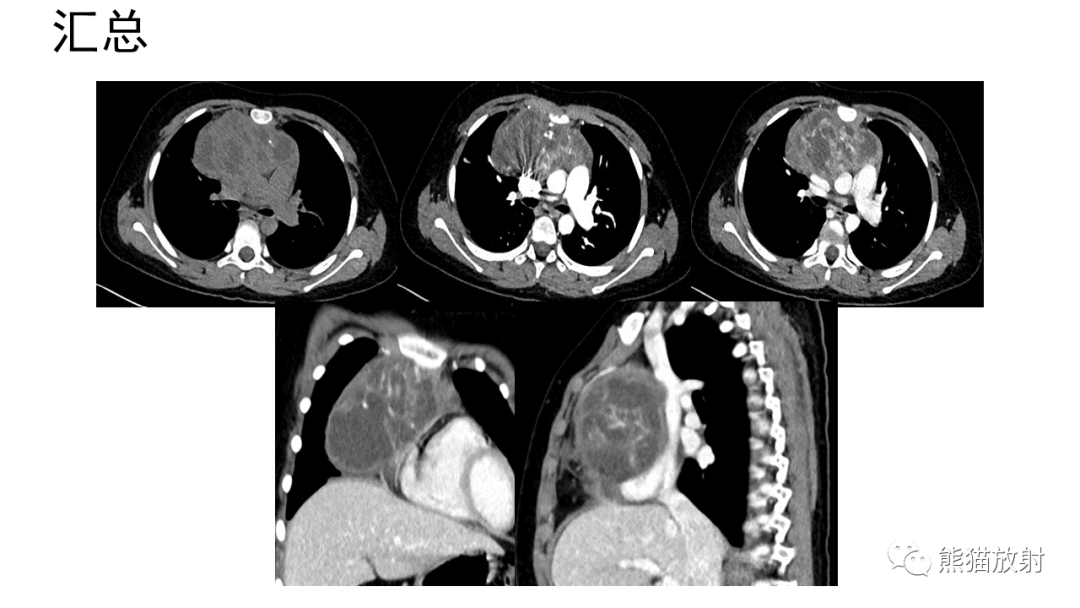

前纵隔畸胎瘤2例CT影像